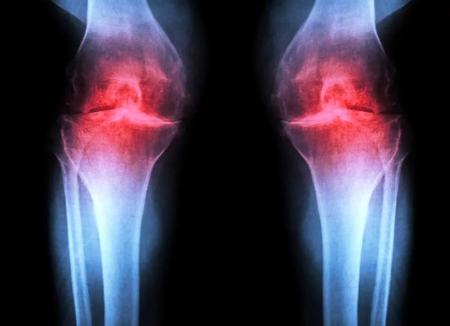

دانشمندان روشی برای بازسازی غضروف شناسایی کردهاند که با هدفگیری پروتئینی که با افزایش سن بیشتر میشود، آسیب مفصلی در حیوانات مسن را معکوس میکند و پس از آسیب، از بروز آرتروز جلوگیری میکند.

به گزارش فرادید، پژوهشگران دانشکدهی پزشکی استنفورد گزارش میدهند که مهار یک پروتئین وابسته به پیری میتواند غضروفی را که بهشکل طبیعی در زانوی موشهای مسن تحلیل میرود، بازسازی کند. در این مطالعه، درمان تزریقی نهتنها غضروف را دوباره ساخت، بلکه پس از آسیبهای زانو نانند پارگی رباط صلیبی قدامی (ACL) که در ورزشکاران و بزرگسالان فعال شایع است، از بروز آرتروز هم جلوگیری کرد. نسخهی خوراکی همین درمان هماکنون در کارآزماییهای بالینی با هدف درمان ضعف عضلانی مرتبط با افزایش سن در حال آزمایش است.

این درمان بهجای تسکین نشانهها، عامل زمینهای آرتروز را هدف میگیرد. این بیماری حادشونده مفصلی حدود یکپنجم بزرگسالان ایالات متحده را درگیر میکند و سالانه حدود ۶۵ میلیارد دلار هزینهی مستقیم مراقبتهای سلامت ایجاد میکند. در حال حاضر هیچ دارویی وجود ندارد که بتواند روند بیماری را متوقف یا معکوس کند و مدیریت درد و تعویض مفصل گزینههای اصلی درمان هستند.

آرتروز زمانی رخ میدهد که مفصل بر اثر پیری، آسیب یا چاقی تحت فشار قرار گیرد. کندروسیتها شروع به آزادسازی مولکولهای پیشالتهابی و تجزیهی کلاژن (پروتئین ساختاری اصلی غضروف) میکنند. با از دست رفتن کلاژن، غضروف نازک و نرم میشود و التهاب همراه، تورم و درد مفصل را (که از ویژگیهای بارز بیماری است) ایجاد میکند. در شرایط عادی، غضروف مفصلی بهندرت بازسازی میشود. اگرچه برخی جمعیتهای فرضی از سلولهای بنیادی یا پیشسازِ قادر به تولید غضروف در استخوان شناسایی شدهاند، تلاشها برای یافتن جمعیتهای مشابه در غضروف مفصلی موفقیتآمیز نبوده است.

سپس آنها با تزریق یک داروی مولکول کوچکِ مهارکنندهی 15-PGDH به حیوانات پیر (ابتدا به داخل شکم با اثر سیستمیک و سپس مستقیما به مفصل) آزمایش کردند. در هر دو حالت، غضروف زانو که در حیوانات مسن نسبت به موشهای جوان بهطور محسوسی نازکتر و کمکارتر بود، در سراسر سطح مفصل ضخیمتر شد. آزمایشهای تکمیلی تأیید کرد که کندروسیتهای مفصل در حال تولید غضروف هیالین (مفصلی) هستند، نه فیبروغضروفِ کمکارتر.

نتایج مشابهی در حیوانات دارای آسیبهای زانو مانند پارگی ACL که در ورزشهایی چون فوتبال، بسکتبال و اسکی با چرخشهای ناگهانی، توقف یا پرش رخ میدهد، مشاهده شد. اگرچه این پارگیها قابلترمیم با جراحی هستند، حدود ۵۰٪ افراد طی حدود ۱۵ سال در مفصل آسیبدیده دچار آرتروز میشوند.